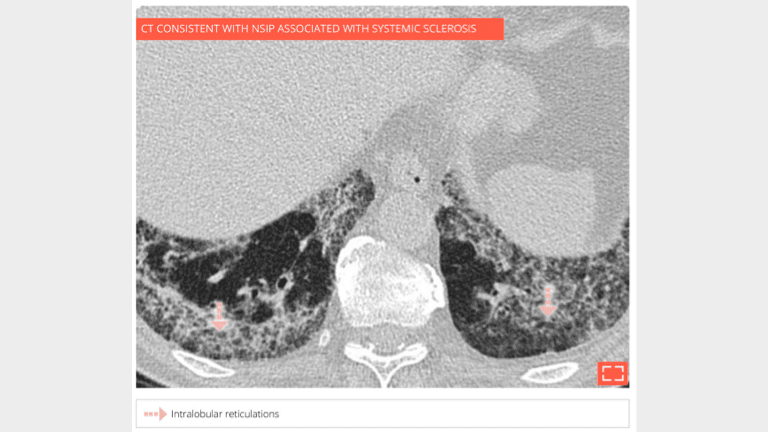

2. Intralobular reticulations

Intralobular reticulations

Marked intralobular reticulations in the 2 lung bases without honeycombing. Note the relative lung savings immediately under pleura, pointing to a NSIP.